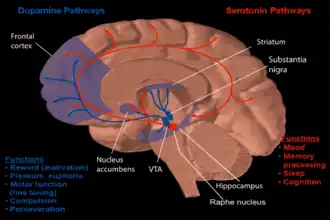

Dopamine and serotonin

Dopamine and serotonin -